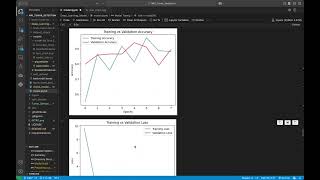

MRI Tumor Detection by Néstor Gómez Artiles

AI-driven brain tumor detection from MRI scans with real-time web predictions.